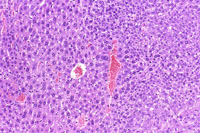

A basophilic adenoma. Basophilic adenomas are often comprised of closely spaced hepatocytes with small amounts of cytoplasm.

A basophilic adenoma.